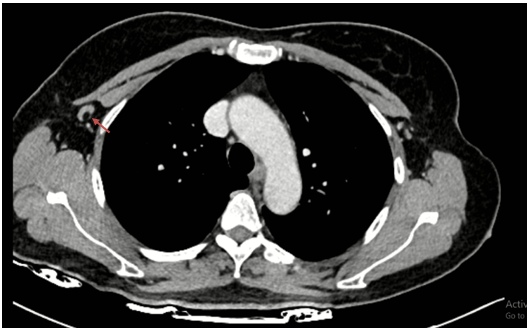

Chụp cắt lớp vi tính lồng ngực có tiêm thuốc: Hình ảnh nốt đặc nhỏ thùy dưới phổi phải. Dải xẹp thùy giữa phổi phải. Nốt ngấm thuốc 1/4 dưới ngoài vú phải đường kính 20mm, bờ ranh giới không rõ, ngấm thuốc sau tiêm.

Hình 3: Hình ảnh nốt ngấm thuốc 1/4 dưới ngoài vú phải đường kính 20mm, bờ ranh giới không rõ, ngấm thuốc sau tiêm (mũi tên đỏ).

Hình 4: Hình ảnh hạch nách phải còn cấu trúc rốn hạch, kích thước ~ 18x7mm (mũi tên đỏ).